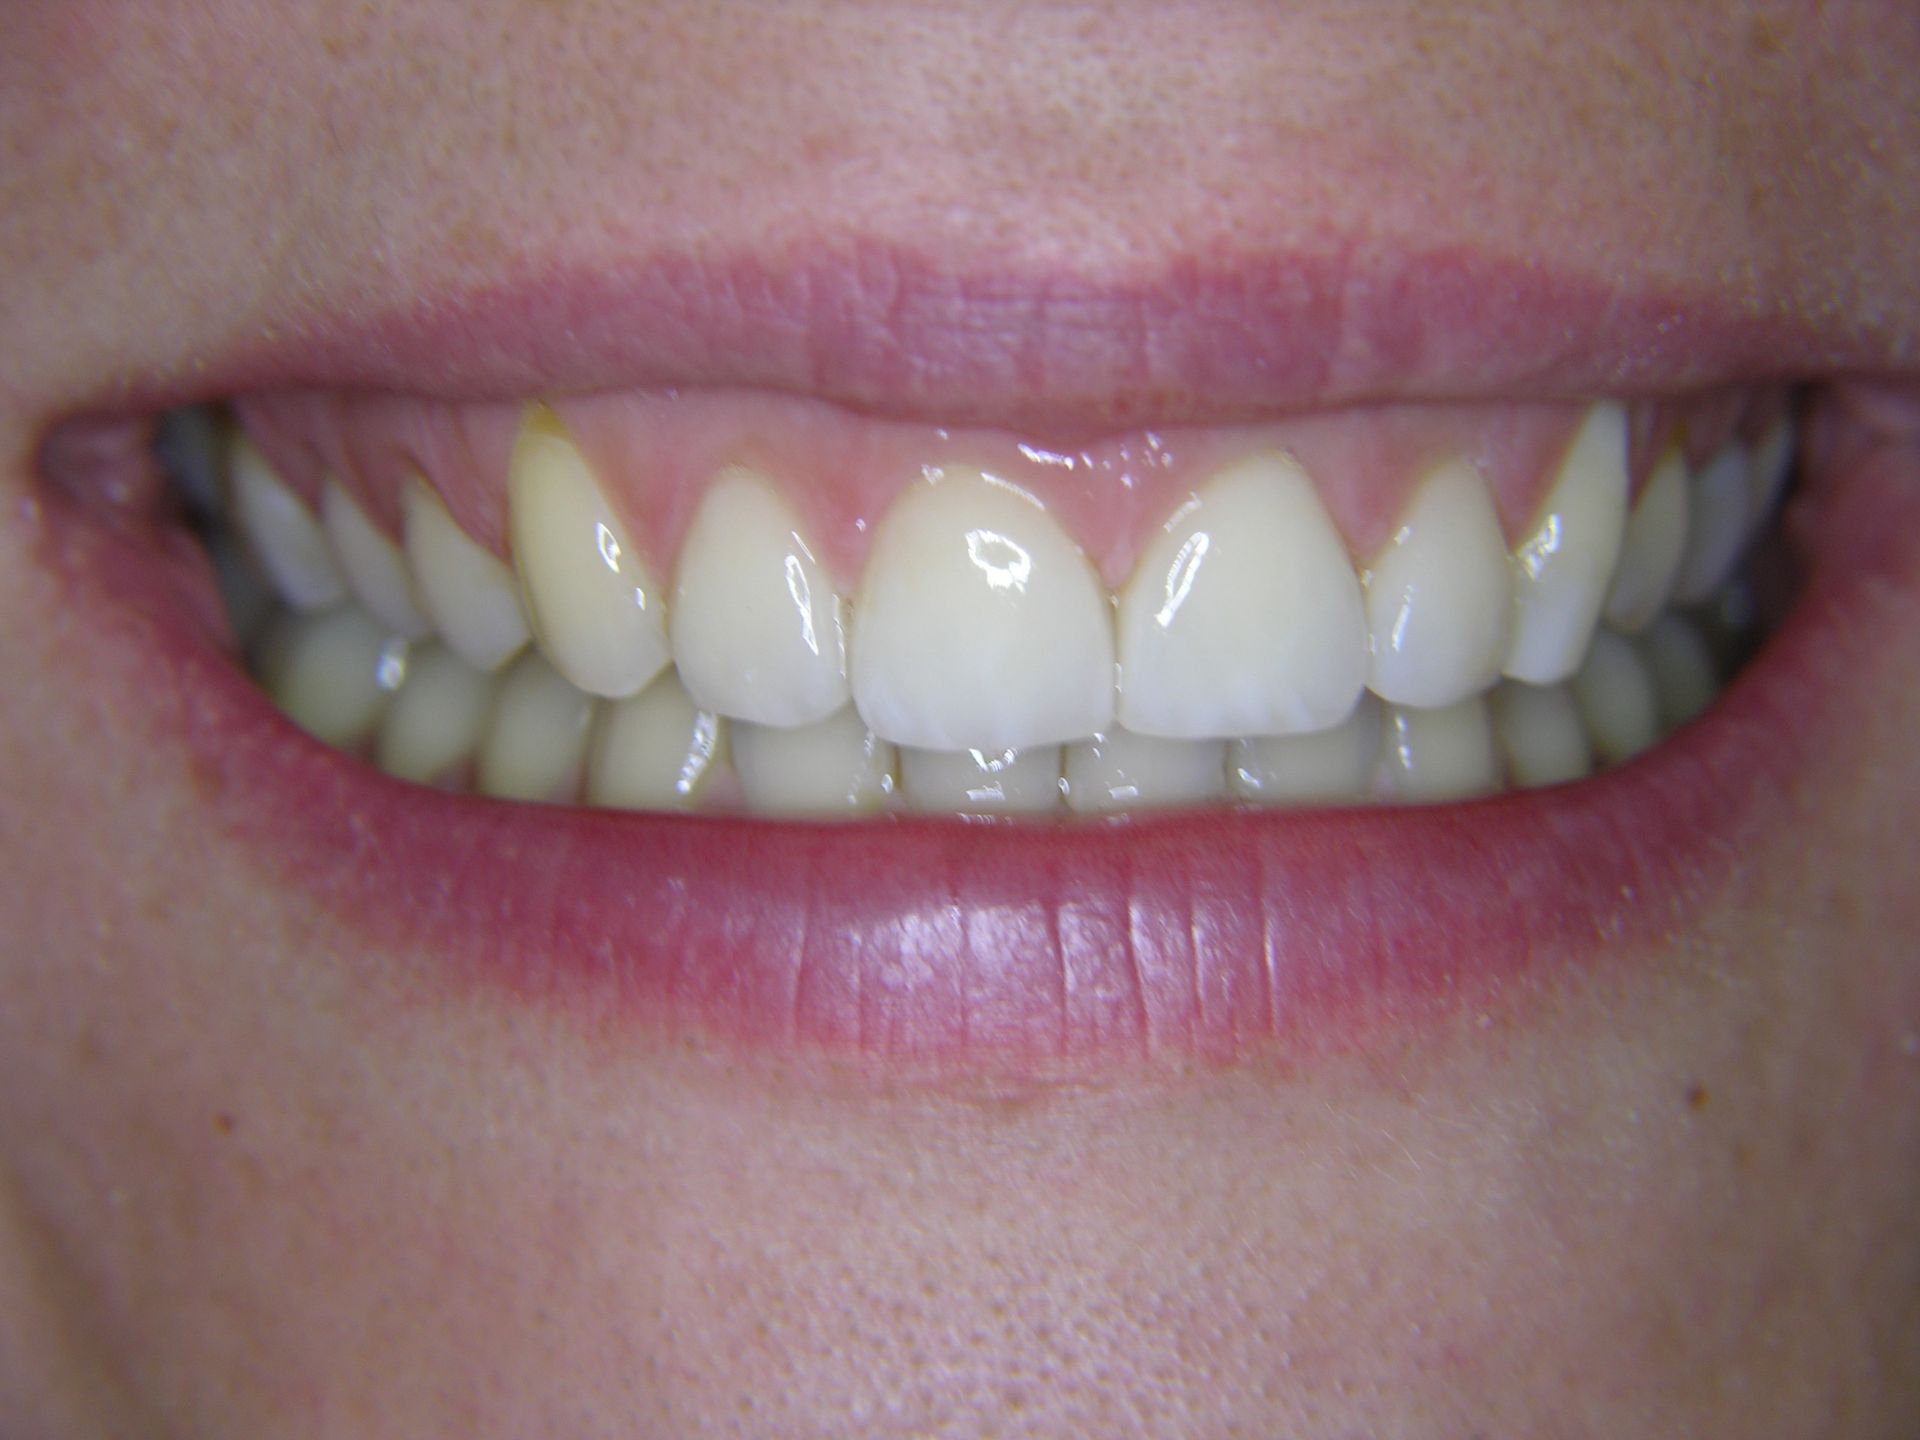

Beispiele von Versorgungen